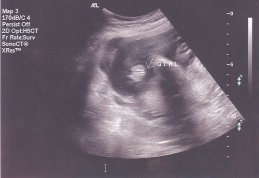

Улыбка писал(а): Аничка, спасибо еще раз, зая! Время так быстро бежит! Даже не верится, что у тебя уже 33 недели!!! Ой Улыбка и не говори.Мне чем ближе срок тем страшнее становится.Больше всего боюсь как моя 2-х летка дочка к братику отнесётся,чувствую 5 точкой ревновать будет по страшному.Она уже как обезьянка на мне в последнее время виснет,везде по пятам да и на ручки просится постоянно.Не было такого у нас раньше,прям как чувствует что ли. Смотри я кстате фотку с дочкиного УЗИ откопала,почти такой же ракурс,ПИРОЖОЧЕК

| Вложения: |

scan0001.jpg [ 16.08 КБ | Просмотров: 1212 ]

anichka писал(а): Смотри я кстате фотку с дочкиного УЗИ откопала,почти такой же ракурс,ПИРОЖОЧЕК  Возможно, что в таком же ракурсе у мальчика будет тоже пирожочек  , но он будет другой, эта полосочка, которая проходит посередине пирожочка будет белая , а у девочек она черная между двух беленьких (думаю понятно объяснила  ).